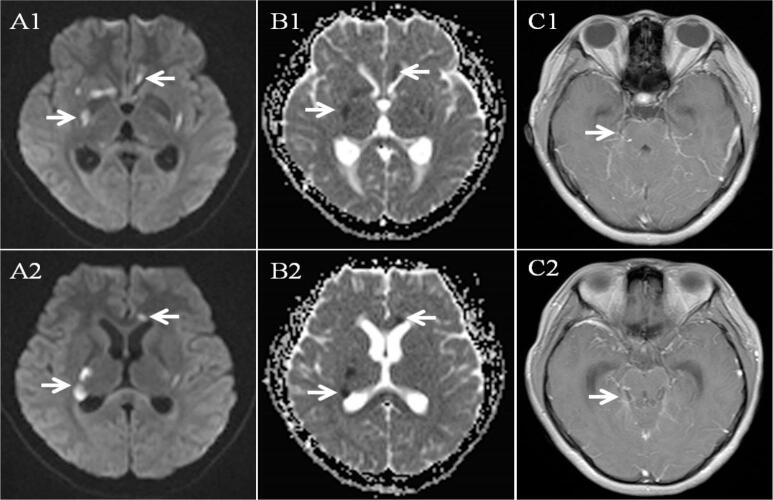

A total of 176 TBM patients were included in the study. Forty-nine patients with stroke were classified as TBMRIS group and 127 patients without stroke were classified as TBM-only group. In TBMRIS group, 41 (83.7 %) patients experienced stroke within 3 months after the onset of meningitis symptoms and 10 (20.4 %) patients presented silent stroke. Stroke occurred in basal ganglia in 57.1 % of patients. About 73.5 % of patients showed multiple stroke lesions and 38.8 % of patients had stroke involving multiple vascular territories. There were significant differences in focal neurological deficit, stage of meningitis, short-term outcome, serum sodium, cerebrospinal fluid (CSF) white cell count, CSF adenosine deaminase (ADA), CSF protein, leptomeningeal enhancement, tuberculoma between TBMRIS group and TBM-only group. Binary logistic regression analysis revealed that focal neurological deficit, CSF white cell count and leptomeningeal enhancement were the independent risk factors for stroke, and tuberculoma was negatively correlated with stroke.

Most of TBMRIS develop within 3 months after the onset of meningitis symptoms and basal ganglia is the most frequent site. Multiple stroke lesions and involvement of multiple vascular territories are commonly observed. Focal neurological deficit, CSF white cell count and leptomeningeal enhancement are the predictors of stroke in patients with TBM.